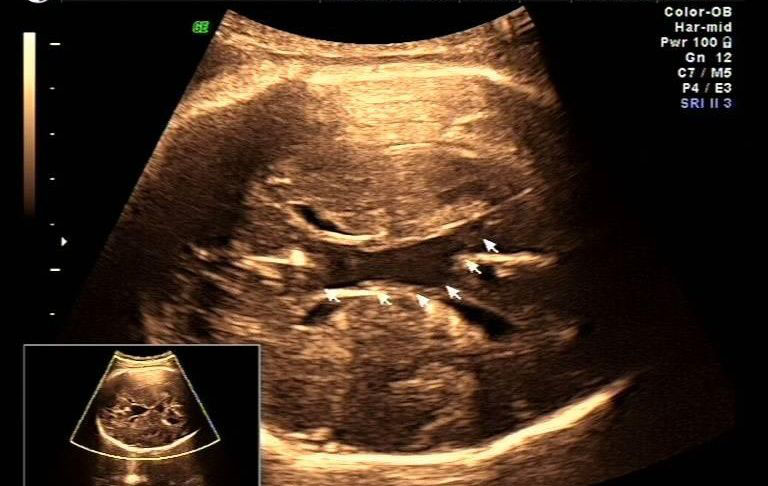

胎儿大脑其他部位是否有畸形。如果大脑沟、回清晰,中线不偏,两边对称,包括小脑、丘部、胼胝体都没有异常,可以考虑继续妊娠。如有包括其他部位的异常,建议做个胎儿磁共振再评估。

有没有局部的囊肿压迫。判断脑室扩张是整个脑室均衡扩张还是局部一个角发生扩张?局部囊肿压迫造成的扩张,可以考虑继续妊娠,但重点要观察囊肿有没有继续增大。